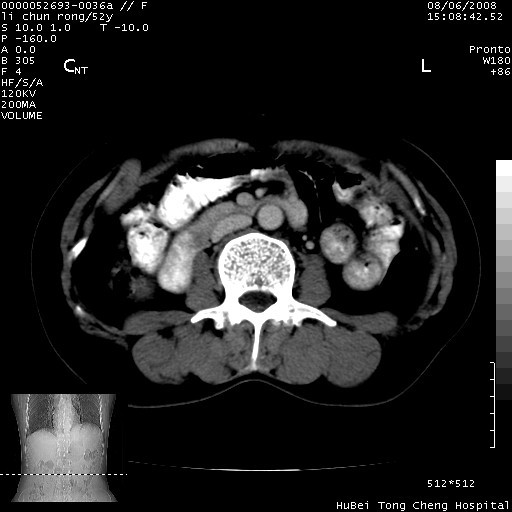

以下是引用云翔在2008-8-7 6:20:00的发言:[br]胰尾部囊性病变,考虑假囊肿,结合实验室检查疾病史

以下是引用zjzjr在2008-8-7 8:38:00的发言:[br]支持胰腺炎伴假囊肿形成,左肾小囊肿.少量腹水.

以下是引用随光逐影在2008-8-7 9:12:00的发言:[br]1)考虑胰腺炎伴假性囊肿形成可能性大;胰腺囊腺瘤待排。2)左肾小囊肿。3)少量腹水。